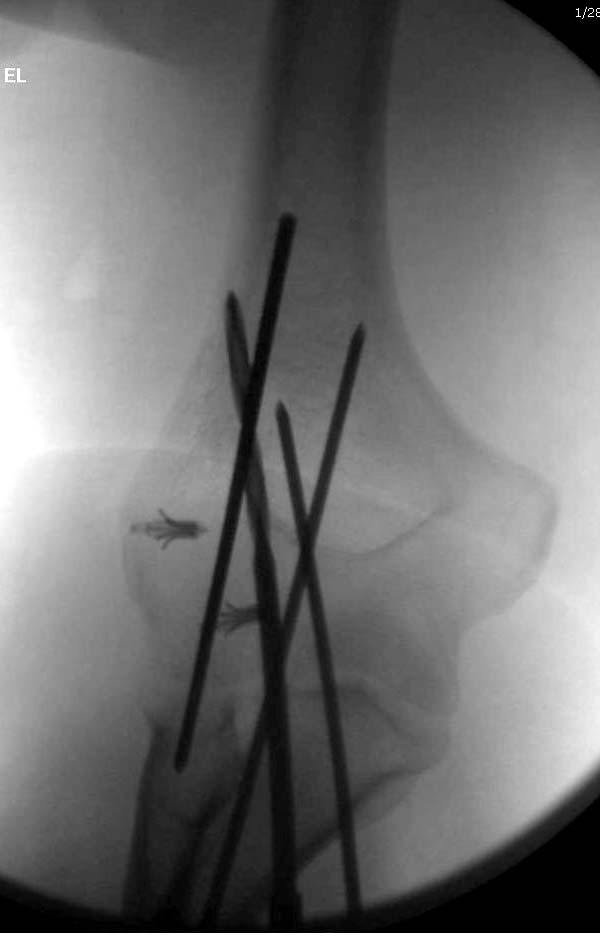

Для примера здесь случай начатый в другом центре, а потом переправленный

к нам.

Снимки: 1-2 вывих, 4-5 вторичное смещение в гипсе, реконструкция

латеральной связки и капсулы 13-14, повторный вывих после реконструкции,

перевод в наш центр; 18-21 временная фиксация, 22-25 трансартикулярная

фиксация и нестабильная головка фиксирована спицами, 29-30 амбулаторно,

32-33 после удаления винта и спиц...

Несмотря на отрицательный отзыв, некоторые нестабильные вывихи лечим

трансартикулярным методом. Тонкие спицы ломаются и имеют риск

внутрисуставной инфекции. Винты 3.5 мм не выдерживают, а более толстые

каннюлированные винты неплохо проявили себя. Неосторожность при

установке приводила к поломке тонких guide wire внутри сустава. Лучшие

кортикальные в 4.5 мм и гипс на три недели. Винт удаляется, затем

разработка сустава.